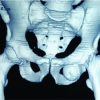

A 40-year-male sustained an open Grade 3 vertical fracture of the right patella which was partially comminuted with an ipsilateral lateral femoral condyle fracture. It was a farmyard injury with penetration of metallic hook of a tractor with bone loss at place of injury discarded by the patient. There was no neurovascular deficit. The patient underwent emergency surgery after anesthesia clearance. The open wound was extended as needed for exploration and fixation. Intraoperatively, it was found that half of the patella was missing, the remaining half had few soft-tissue attachments and there was a defect in the articular surface of the lateral femoral condyle as shown in the image. As the patella was not salvageable, it was decided intraoperatively to do a patellectomy and use it as a bone graft to recreate articular surface of the femoral condyle. The lateral femoral condyle was reduced and fixed using cancellous screws and bone grafted patella was reshaped and positioned in the defect such that articular cartilage faces outward and held in place using K-wires which were left buried in situ. Tendon ends were repaired using non-absorbable sutures and patient was immobilized in a knee brace for 6 weeks. Static quadriceps was started from 1st post-operative day. Knee range of motion was started at 6 weeks. Partial weight-bearing started at 1.5 months and full weight-bearing at 2.5 months. The patient was advised to wear a removable knee brace while walking. At review 1 year after the injury, the patient had 100° of knee flexion with a 10° extension lag, was independently ambulatory, and complained of occasional pain and instability (Fig. 1a-d).